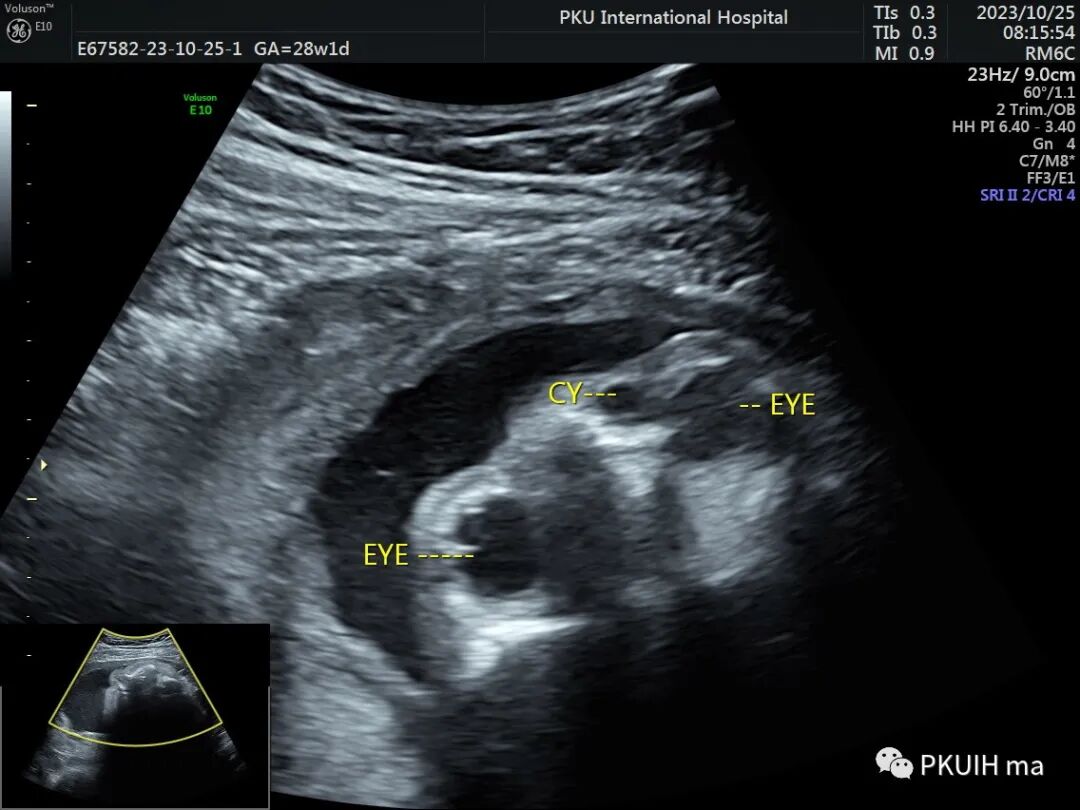

在晚孕期超声经常能发现胎儿眼眶内下方鼻旁处有小的无回声区,可以双侧也可以单侧,这种是非常常见的胎儿鼻泪管囊肿。

鼻泪管囊肿一般在孕晚期常见,多数在自动消失,主要是由于鼻泪管远端堵塞所致。最常见的是近Hasnei瓣外的一层黏膜阻断导管,引起鼻泪管囊状扩张,从而形成囊肿。超声表现为眼内下方鼻骨旁见圆形或类圆形无回声,大小一般小于1cm,内透声良好。随孕周增加超声复查可以消失或变小,极少部分至足月分娩时仍可见。